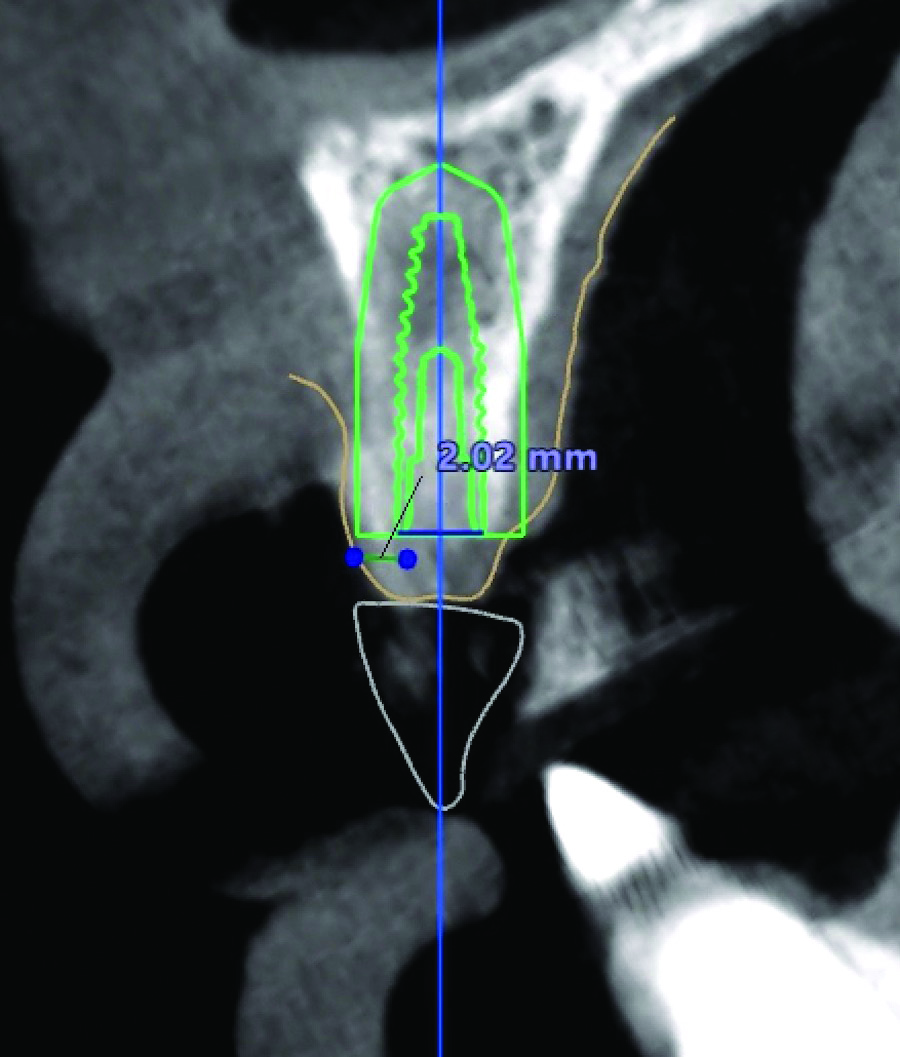

MT can be measured directly after a surgical flap elevation with an instrument such as a ruler or indirectly during a treatment planning stage with a digital measuring tool in an implant treatment planning software program (Figure 4 and Figure 5). As with KMW, it has been proposed that at least 2 mm of MT be present, although a lack of literature exists regarding its minimum dimension.8

An example of an implant treatment planning case is presented in Figure 2 and Figure 4, with Figure 2 showing a digital scan of a mandibular arch that includes a missing tooth No. 19. The scan shows there was adequate KMW (>2 mm) at the No. 19 area. The digital scan of No. 19 was superimposed with a cone-beam computed tomography (CBCT) scan to analyze the future implant site. Upon superimposition, the MT could be measured at any surface (Figure 4). MT at the direct buccal and direct lingual aspects of the peri-implant mucosa was measured at >2 mm. The simulated future implant placement and the outlined safety zone of 1.5 mm radially and 2 mm apically around the implant indicate that the thickness of bone at the implant site was sufficient as planned. This case demonstrates there was enough KMW, bone thickness, and MT to proceed with implant placement.

Another example of an implant treatment planning case, on a missing tooth No. 7, is shown in Figure 3 and Figure 5. There was adequate KMW (>2 mm) in the area of the missing tooth, but a concave contour was present on the buccal aspect of the ridge at the crest (Figure 3). A digital tooth set-up for the missing tooth No. 7 was superimposed with a CBCT. Upon superimposition, the MT could be measured at any surface (Figure 5). The simulated future implant placement and the safety zone marked around the implant indicate the thickness of the bone at the implant site was sufficient as planned. The MT, however, was <2 mm with clinical presence of a lack of soft-tissue volume. This clinical example demonstrates the need for soft-tissue enhancement to increase MT.

Fig 4. Digital tooth setup; the digital scan in Fig 2 was superimposed with a CBCT. The blue dots with green horizontal lines indicate MT measurements (2.04 mm and 2.02 mm). The simulated implant (green diagram of a dental implant with threads) and safety zone (green outline around the diagram of the implant) are overlaid on a cross-sectional image of the alveolar ridge. The red circle indicates the inferior alveolar nerve canal.

Fig 5. Digital tooth setup for missing tooth No. 7 in Fig 3, superimposed with a CBCT. The blue dots with green horizontal line indicate MT measurement (1.03 mm). The simulated implant (green diagram of a dental implant with threads) and safety zone (green outline around the diagram of the implant) are overlaid on a cross-sectional image of the alveolar ridge.